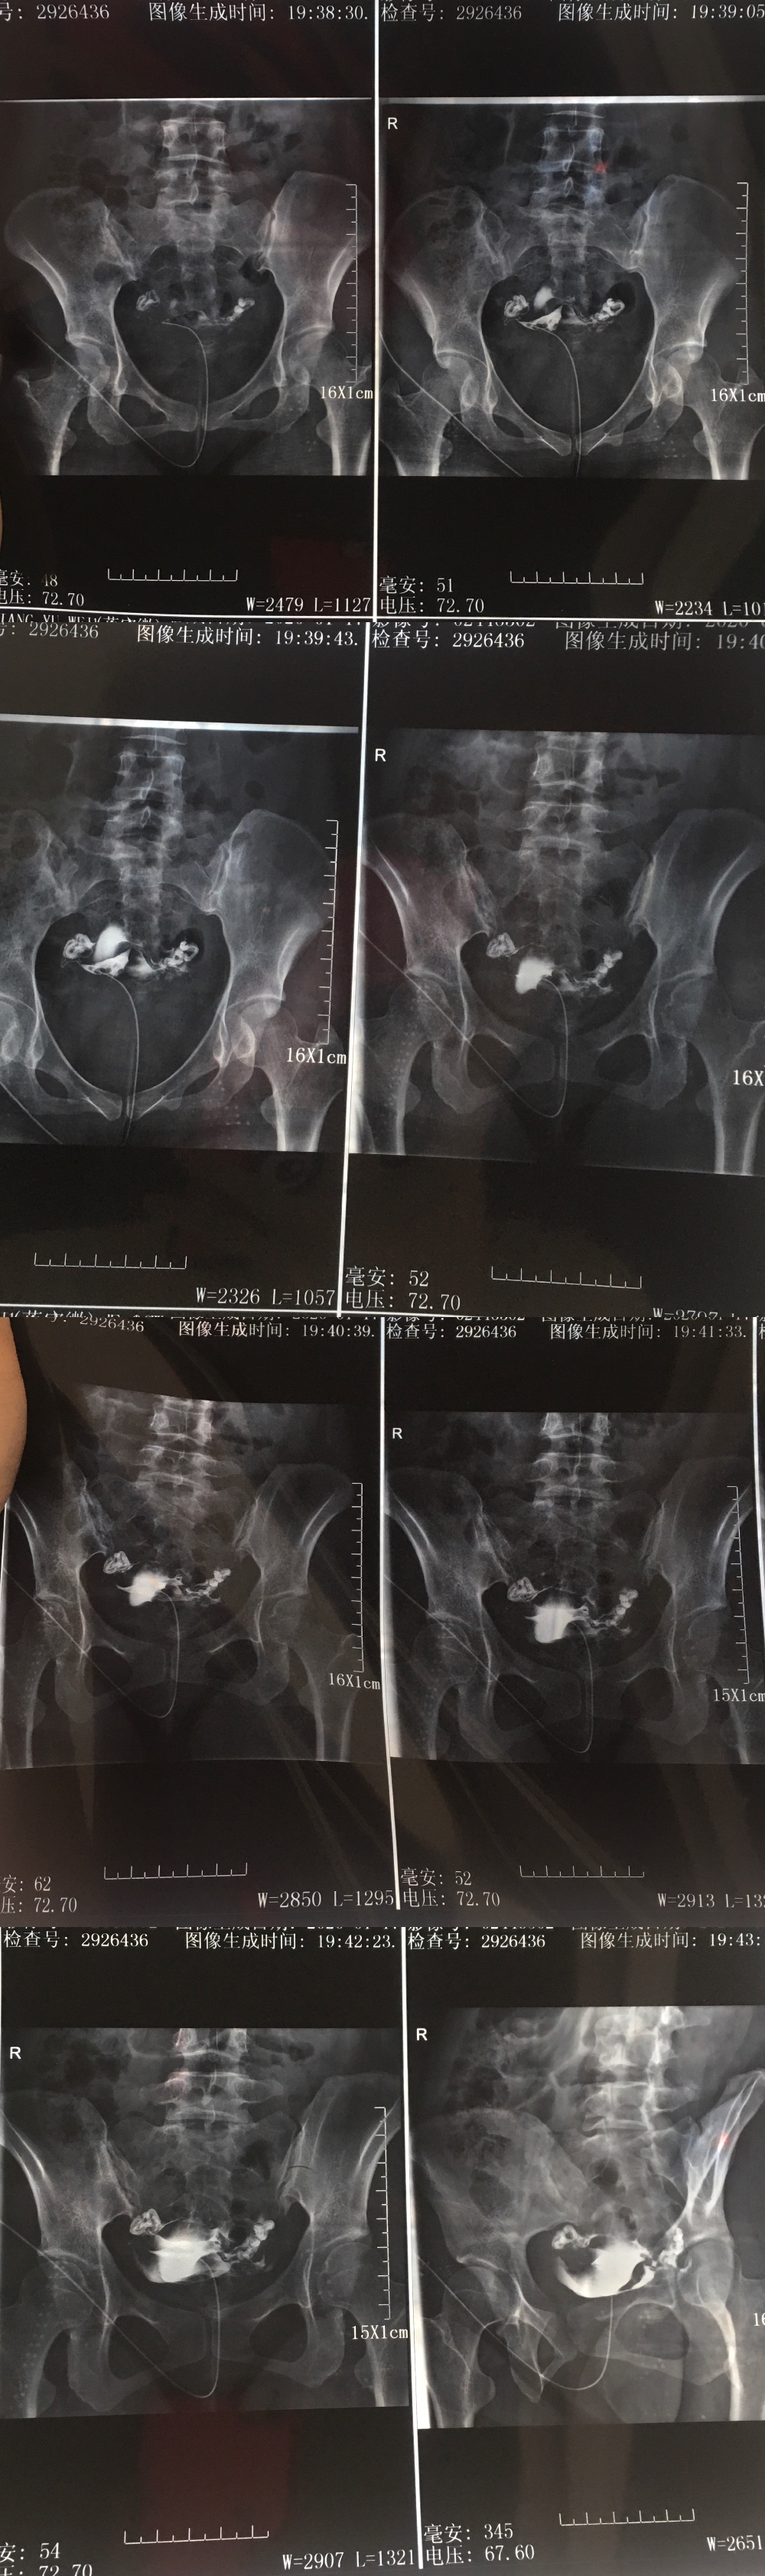

分析一下输卵管造影片给出下一步治疗方案

分析一下输卵管造影片,给出下一步治疗方案